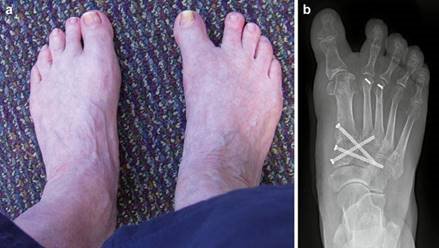

Hallux varus, characterized by medial deviation of the hallux, is an iatrogenic complication that is deeply frustrating for both the surgeon and the patient. It is typically the result of a "staged" error: over-resection of the medial eminence past the sagittal sulcus, combined with over-plication of the medial capsule and complete transection of the lateral collateral ligament. Flexible deformities can occasionally be managed with an extensor hallucis brevis (EHB) tenodesis, while rigid deformities inevitably require arthrodesis.

Image

Hallux Varus 2 - 8% Over-resection of medial eminence; Over-tightening of medial capsule; Aggressive lateral release. Early: Taping/splinting. Late: EHB tendon transfer; Medial capsule release; MTP Arthrodesis.